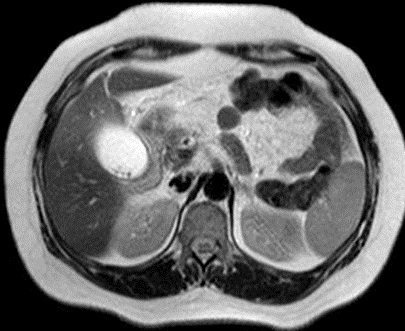

En coupe pondere sur T2 (

l'eau est hypersignal ) on peu en vue la vesicule

biliaire est distendue ,hyperintense tres net

et image de dilatation legere de voie biliaire

intra- hepatique |

Le calcul est en hyposignal

tres grand et arrondie en compressant le canal

hepatique commun . Image radiologique IRM pondere

sur T2 . |

Meme cas en coupe IRM a T2 coronal . La

vesicule biliaire est distendue et hyperintense . Le

calcul est en compessse sur la voie biliaire

principale . Le canal hepatique commun et voie

biliaire en amont est en leregement dilate . |